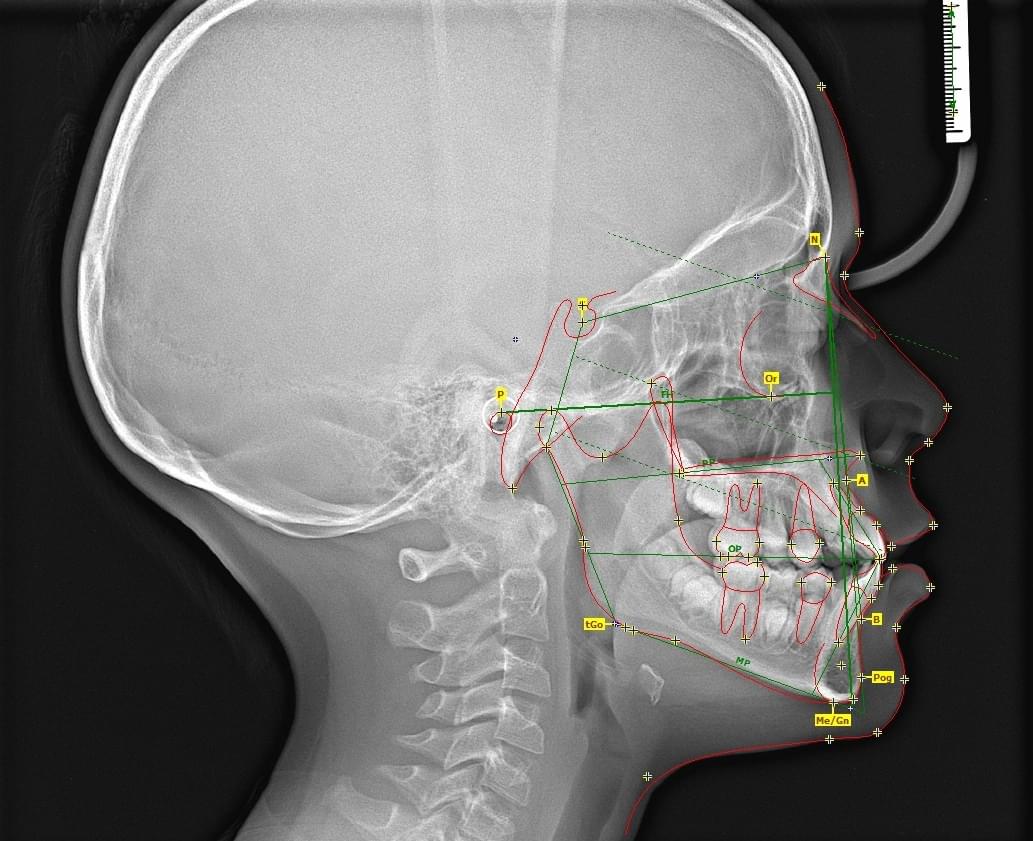

3D цефалометричний аналіз є сучасною технологією, яка дозволяє отримувати точніші,

комплексніші та надійніші дані про зубну та скелетну структуру. Ця технологія може стати

великим кроком в перед для ортодонтів, які хочуть забезпечити найкраще можливе лікування

своїх пацієнтів.

Основні переваги 3D цефалометричного аналізу:

Точність: 3D цефалометричний аналіз забезпечує точніше визначення розмірів та відстаней між

зубами та кістковими структурами.

Комплексність: ця технологія дозволяє отримувати детальні дані про різні структури, такі як

кістка та м'язи, що дозволяє ортодонтам докладніше досліджувати деякі патології та планувати

лікування.

Надійність: 3D цефалометричний аналіз дозволяє отримувати надійніші результати, оскільки

виключає можливість помилок, пов'язаних зі спотворенням або перекриттям зображень.